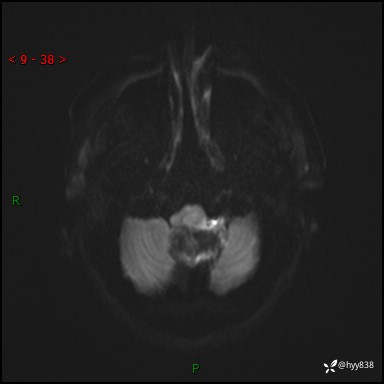

性别:女

年龄:47岁

简要病史:头晕1年余,间断恶心不伴呕吐

颅脑MRI平扫+DWI

增强(axi+cor+sag)

轴内、轴外占位

病灶的影像特征

轴内或轴外肿瘤